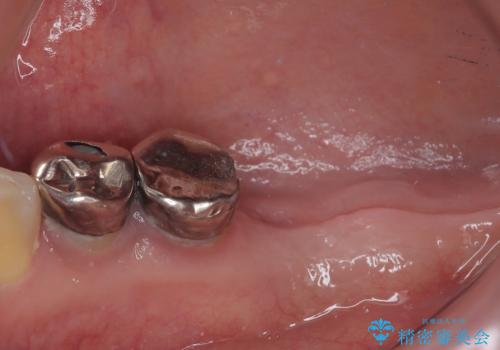

- 「歯を抜いたので、インプラントを入れてほしい」という主訴で来院された患者様です。

他院で歯根破折により抜歯をしたとのことでした。

CTにより残存骨量を確認しインプラント埋入を行っていくこととしました。

今後手前の根管治療を行っている歯が歯根破折を起こして抜歯になる可能性を想定して手前の歯に平行にインプラント埋入を行っています。